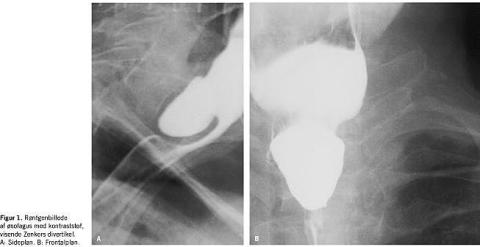

Den første anatomiske beskrivelse af et pulsionsdivertikel i øsofagus blev givet af Ludlow [1] i 1769. I 1878 beskrev Zenker [2] den basale patofysiologi ved udvikling af pulsionsdivertiklet, som senere blev opkaldt efter ham. De fleste Zenkers divertikler er lokaliseret opadtil på overgangen imellem hypopharynx og øsofagus. Det drejer sig om uægte divertikler, idet ikke alle lag i øsofagusvæggen findes i divertikelvæggen, muskulaturen mangler. Divertiklerne ses overvejende hos ældre patienter. Symptomerne er synkebesvær, som forværres efter nogle mundfulde, efterhånden som divertiklet fyldes med føde. Herved komprimeres lumen i øsofagus, og føden kan ikke passere. Typisk for patienter med Zenkers divertikel er progredierende vægttab og regurgitation af ufordøjet føde. Diagnosen stilles ved den typiske anamnese og verificeres ved hjælp af røntgenundersøgelse af øsofagus med kontraststof (Figur 1 ).